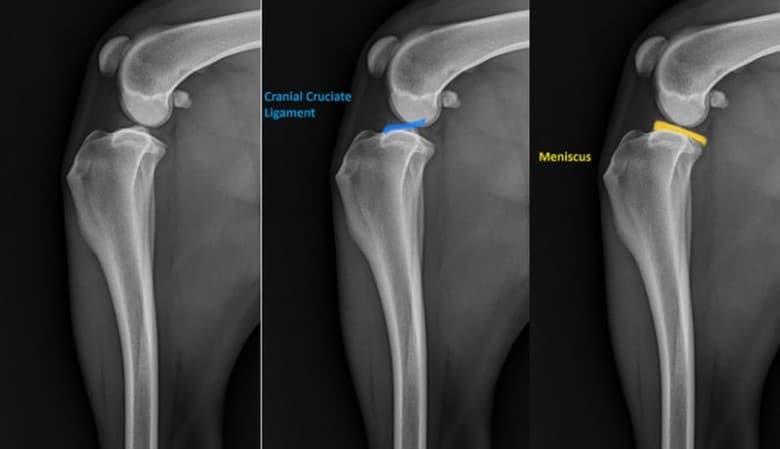

The cranial cruciate ligament (CCL) is the dog version of the human ACL. It:

- Stops the tibia (shin bone) from moving forward

- Keeps the knee from twisting

- Supports the stifle joint when walking and running

In case the CCL is torn – either partially or completely – the knee lacks mechanical stability, thus leading to dog knee instability and the gradual worsening of the joint.

- X-rays (to evaluate swelling and arthritis)

X-rays do not depict the ligament directly but help identify joint instability and arthritis, which are typical of dog knee instability.